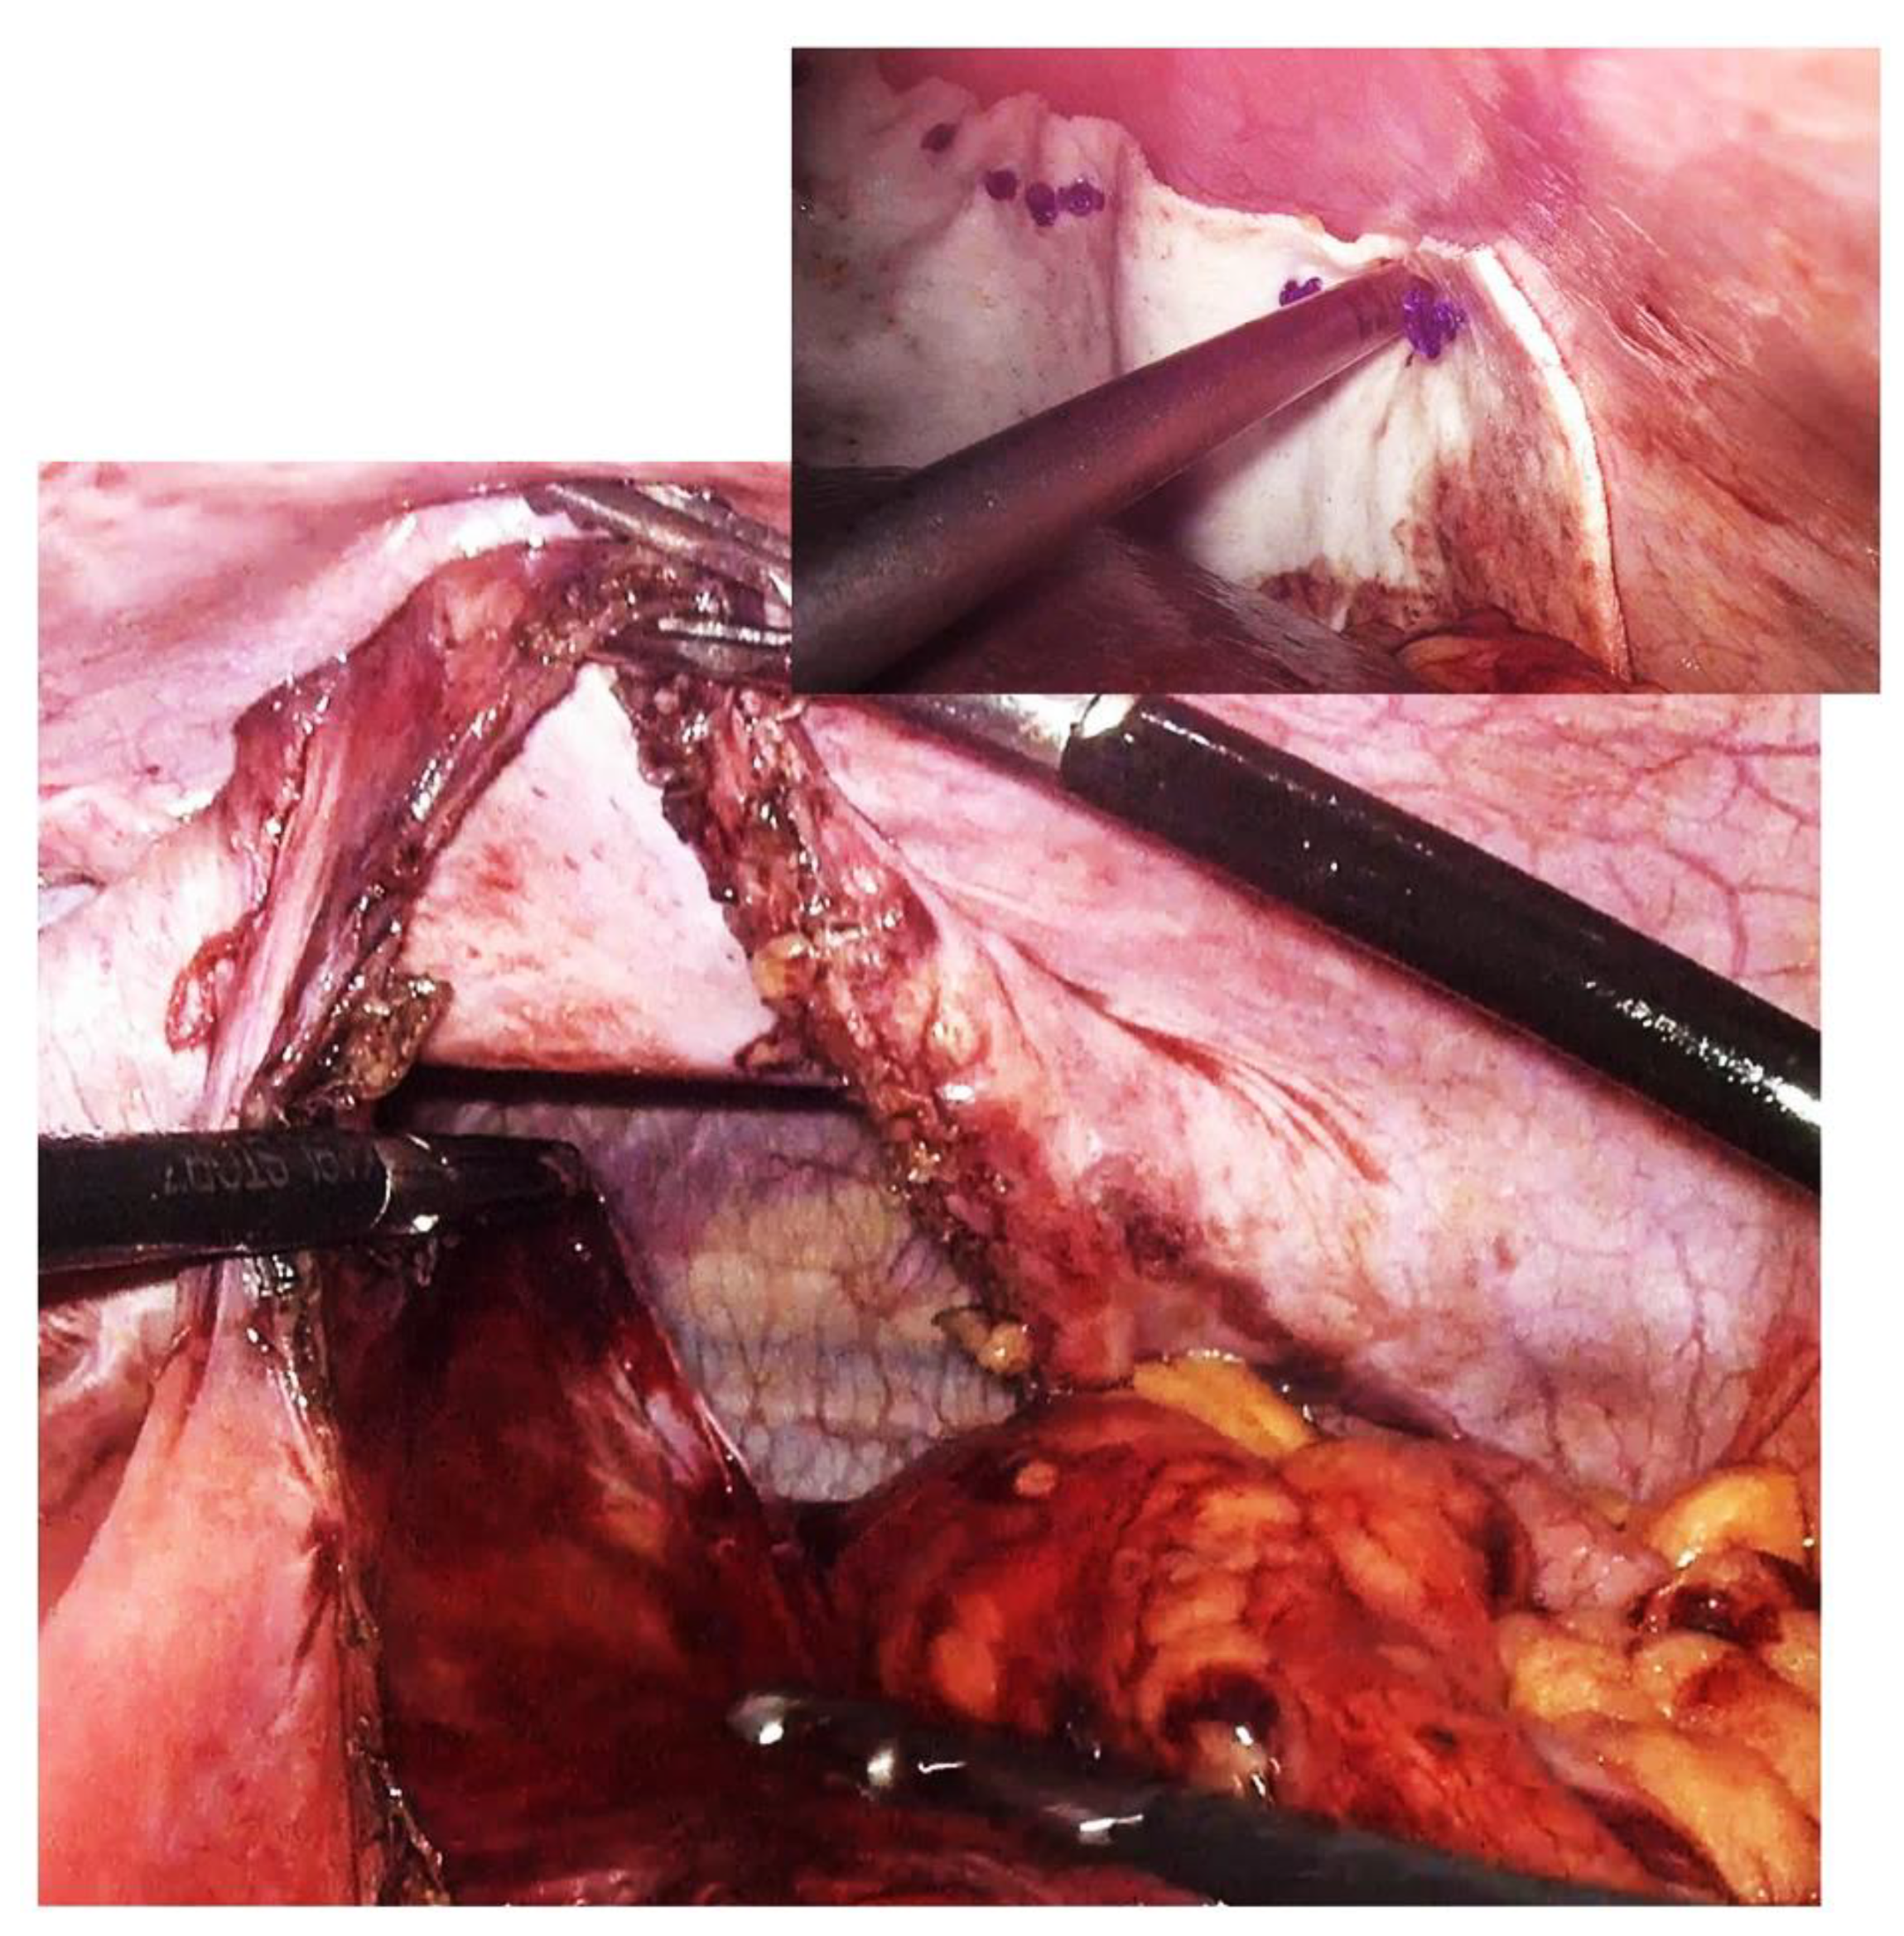

Approach options are the thoracic, abdominal, or combined thoraco-abdominal approach, classic or minimally invasive [22]. The advantages of the thoracic approach over the abdominal approach are direct visualization of the hernial contents and non-negative intrapleural pressure, which facilitates reduction. Through the thoracic approach, adhesions between herniated viscera and the lung or pleura can be safely dissected, although few intrapleural adhesions have been found in previous reports. On the other hand, the thoracic approach in its classic version has the disadvantage of a much more “aggressive” technique for the patient; it forces selective intubation, a surgical gesture limited by the intercostal access, an often much more complex resuscitation, and a difficult, long recovery. In contrast, the advantage of the abdominal approach is the easier recognition and management of possible strangulated bowel loops or concomitant abnormalities of the abdominal viscera [23]. The abdominal approach is more commonly used than the thoracic approach and may be more appropriate in complicated cases with strangulation, ischemia, or visceral abnormalities. Minimally invasive thoracoscopic, laparoscopic, or robotic surgical interventions have slowly become the procedures of choice and are increasingly used on both sides of the diaphragm [24] due to their well-known advantages (Figure 4). The presence of strangulation, volvulation, and perforation are formal contraindications to a minimally invasive technique, but here it must be judged on a case-by-case basis [25,26,27].

Figure 4. Intraoperative aspect of laparoscopic surgery for Bochdalek diaphragmatic hernia—the diaphragmatic defect of about 18 cm is highlighted. In the smaller image is the final appearance after primary suture of the defect and reinforcement with biological mesh.